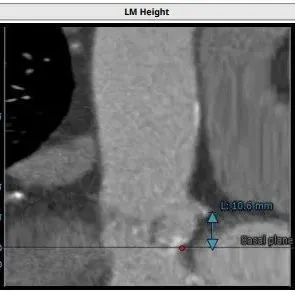

左冠高度:10.6mm,右冠高度:14.5mm。